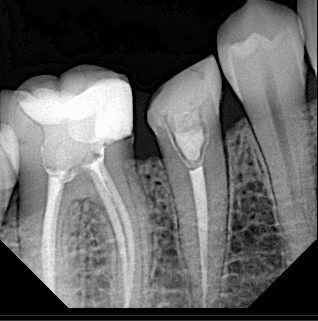

After preparing the tooth

Final x ray